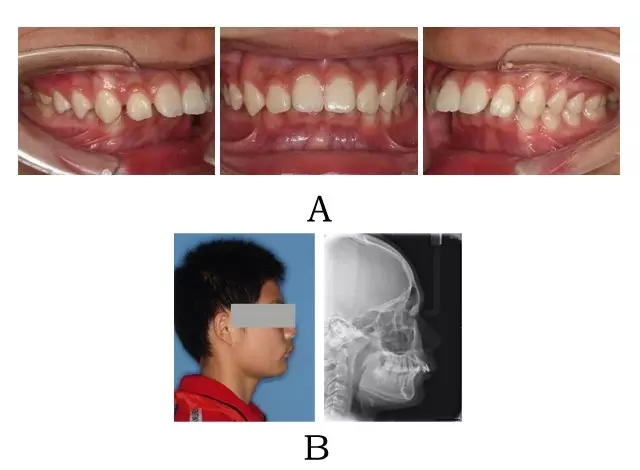

面型前突,面下部高度不足,頦唇溝較深??趦?nèi)表現(xiàn)為上頜骨源性前突,上前牙代償性直立或輕度唇傾;下頜后退伴深覆合深覆蓋,磨牙系遠(yuǎn)中關(guān)系。頭顱側(cè)位片下頜骨體部呈“長(zhǎng)方形”,頦部形態(tài)較好(圖 4-1)。

圖 4-1:混合 I 型突面畸形臨床表現(xiàn)及頭顱側(cè)位影像特征。

(A)齒槽與牙列特點(diǎn) (B)側(cè)貌與影像對(duì)比

Figure 4-1. Clinical manifestation and cephalometric image for merged skeletal and mandibular positional prognathism (Type I). (A) Alveolar and dentition specifics. (B) Facial profile and radiographic image.